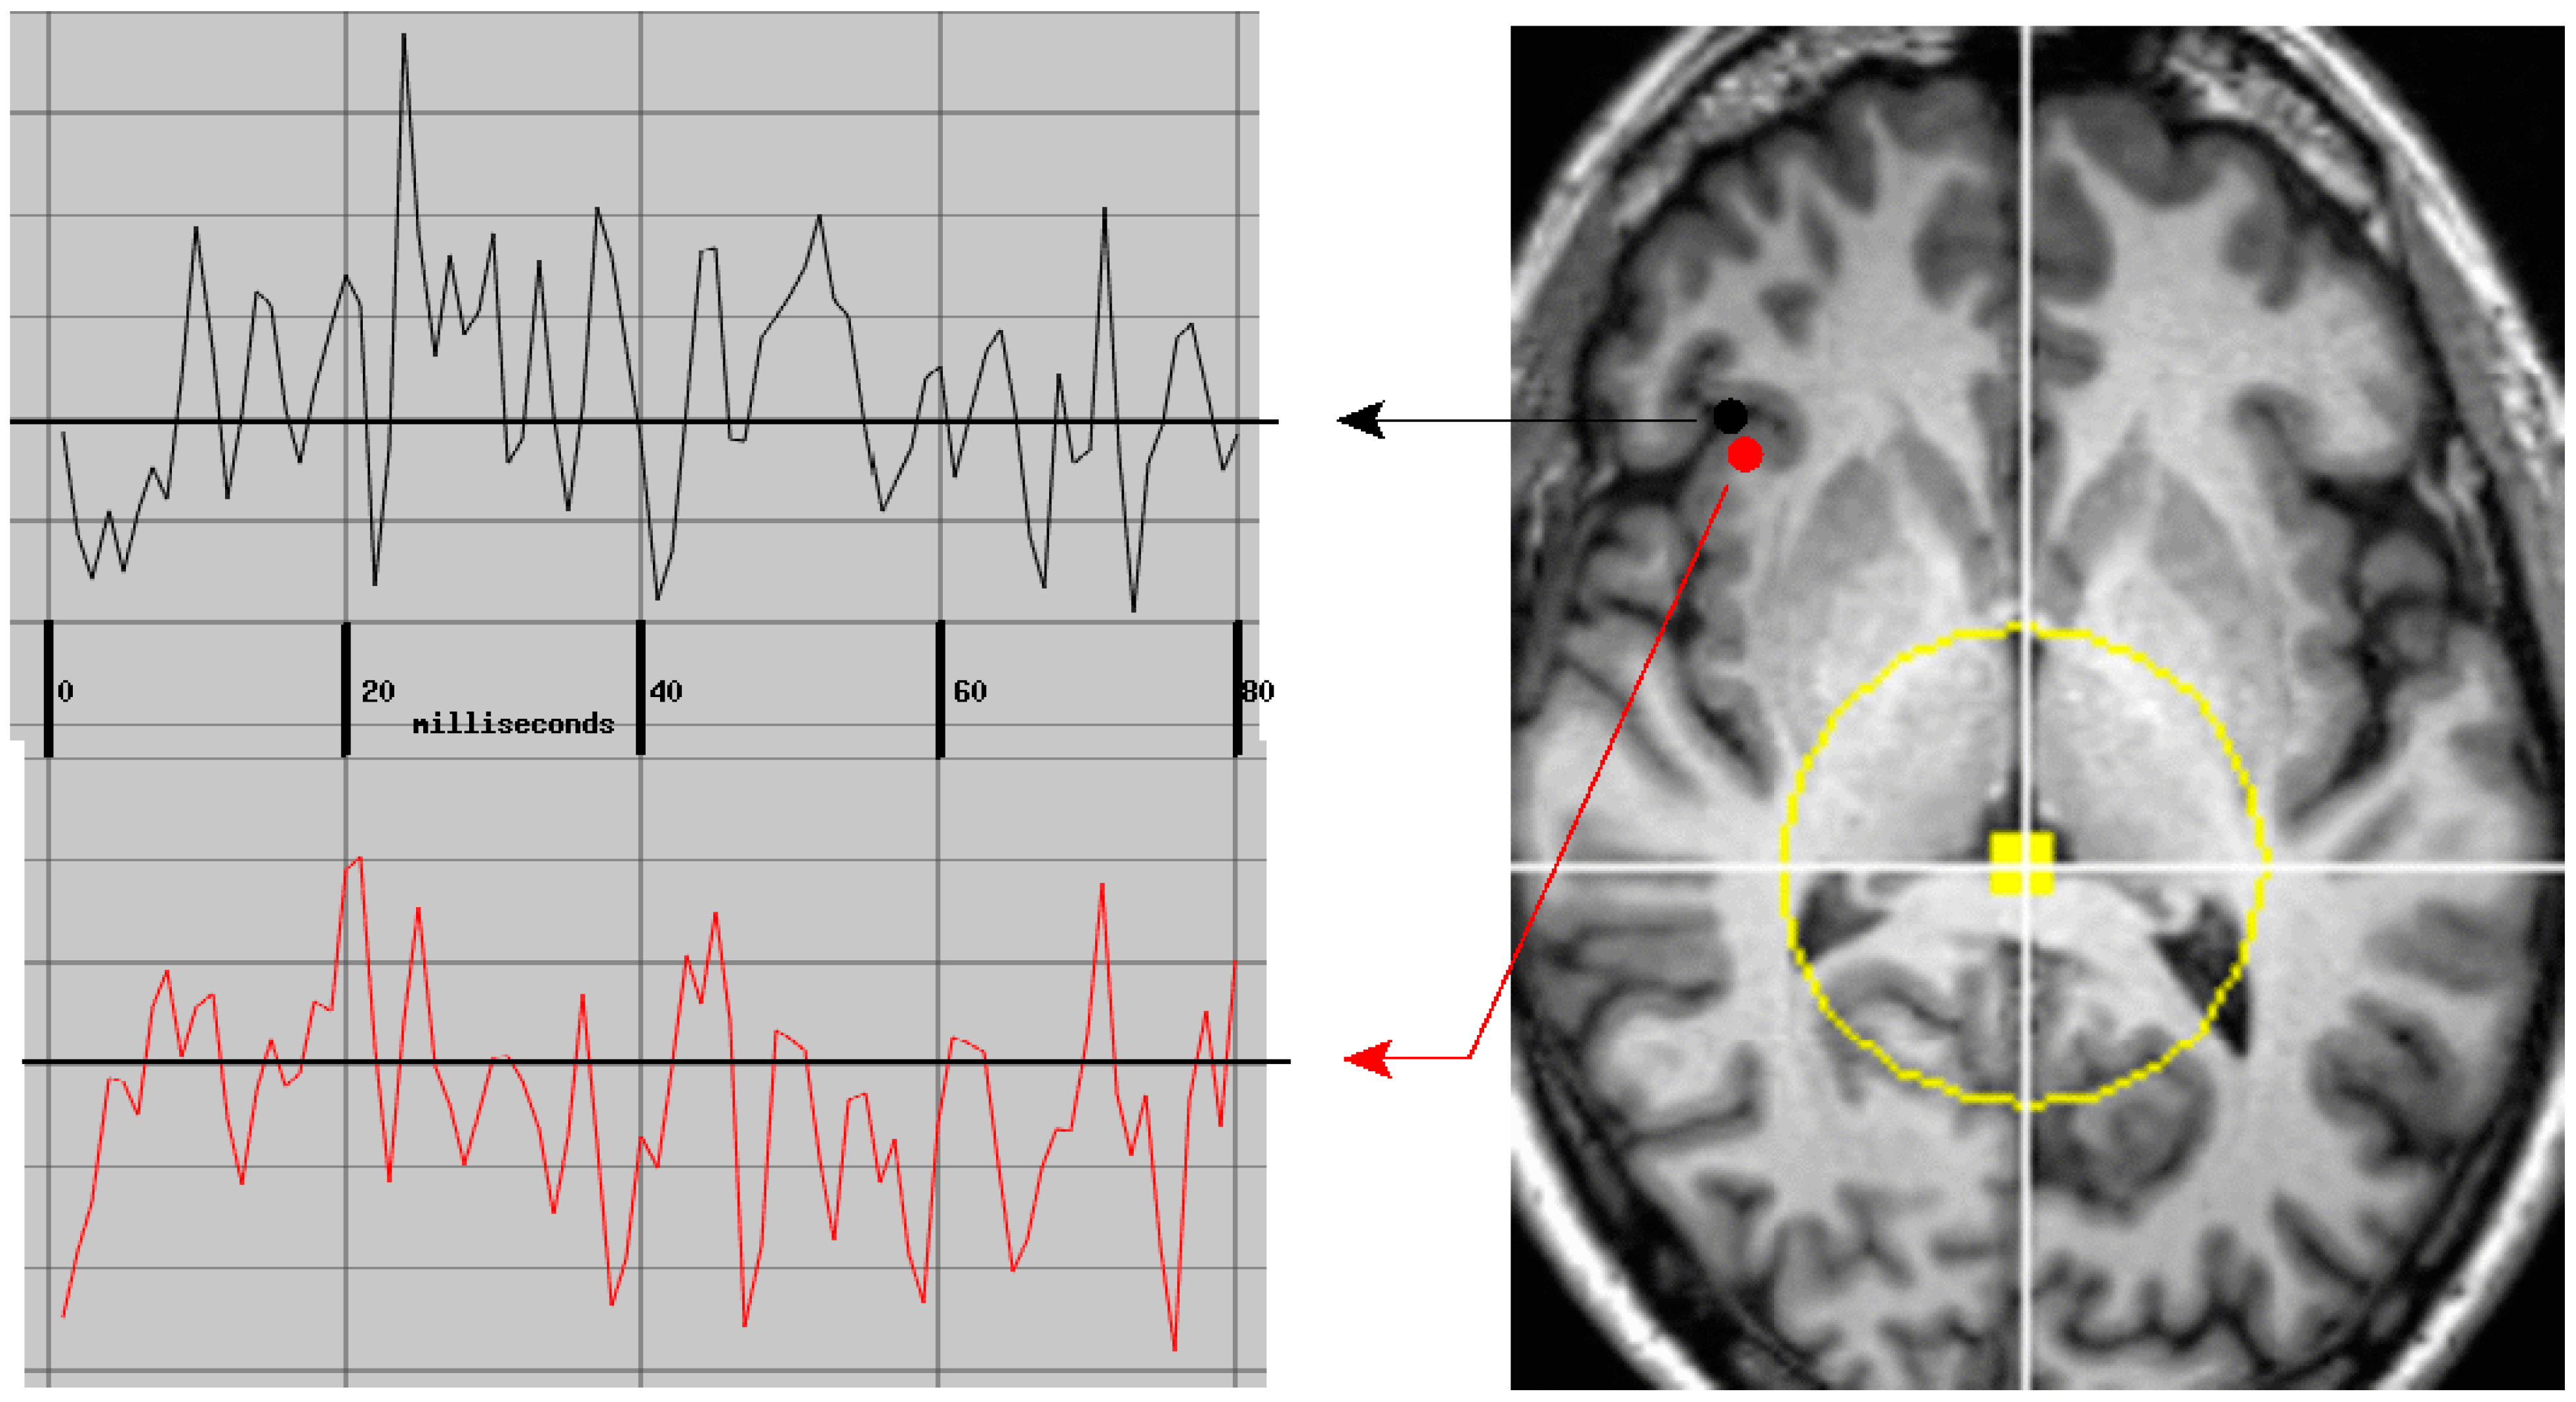

The raw MEG data from each subject were initially transformed to a collection of probabilistically validated neuroelectric currents. Each current is 80 msec in duration and is localized in time and space with a resolution of one millisecond (msec) and better than 5 mm (mm). This primary processing step yielded profuse high-resolution neurophysiological measures from within the brain of each subject. The total current count per subject per minute is typically in excess of 500,000.

The MEG channels were each filtered using MNE tools with high and low pass at 10 and 250 Hz, 5 Hz roll-off [24]. A value of 250 Hz was used for the low pass to thoroughly remove the continuous head positioning signals present in the raw MEG at 293, 307, 314, and 321 Hz. Previous work has shown that the higher the low-pass frequency, the greater the yield of the solver [8,9]. Note that the 10 Hz high-pass filtering effectively demeans each channel and removes much of the low-frequency content most commonly studied. A value of 10 Hz was used for the high pass because (a) the solver yield significantly increases with the low frequencies removed and (b) the solver was set to search one 80 msec data segment at a time. Data lengths greater than this reduce solver yields [8,9], presumably because current dipole orientation rarely remains stable for that long. This short data length provides very low sensitivity to frequencies below 12 Hz. However, the solver was stepped through the data in 40 msec increments; hence, a bolus of identified current dipoles was identified at 25 Hz. Analysis of the time course of those boluses can provide analysis of low frequencies; however, this is outside the scope of the present study.

The forward solution is the mathematical relationship between a putative electric current within the brain and the resultant magnetic field measurements at the sensor array. The solution we used models the brain as a uniformly conducting sphere [3]. Currents within 30 mm of the center of the sphere are nearly undetectable and the mathematical formulation for the forward solution behaves poorly for this volume; hence, it was excluded from the search. The intersection of this region with an MRI slice is shown in Figure 8. Note that the excluded volume typically includes the posterior thalamus, the posterior commissure, and much of the midbrain (not shown in the figure). The solver’s search volume was delimited using the automated brain segmentation provided by Freesurfer with the 30 mm sphere at the center excluded.

When applied to continuous MEG recordings, the solver typically identifies and validates more than 400 neuroelectric currents within the brain per 40 msec step through the data stream—p < 10−12 for each and p < 10−4 for each when conservatively corrected for multiple comparisons (Bonferroni). This is more than 600,000 currents per minute of recorded MEG data identified with millimeter and millisecond resolutions. Note that data segments contaminated by movement or other artifacts were not manually identified for removal. Instead, artifact rejection relied upon the referee consensus solver’s inherent failure to validate neuroelectric currents when presented with noisy data, as shown in Figure 9 [27].

Under the assumption that the white matter is in fact the source of profuse measurable neuroelectric activity, the measured magnetic field components can only be due to synchronous volleys of APs. These would produce transient longitudinal intra-axonal currents which are nearly synchronous in many parallel running axons due to near simultaneous passage of propagating APs.

The detected magnetic field waveforms, e.g., Figure 8, are envelopes which follow the high-frequency waveforms of several AP volleys in sequence. The envelope of a single highly synchronized AP volley would require well under 10 msec to rise and fall. Hence, this type of activity would be dominated by high-frequency contents. This is consistent with the observation that the yield of the solver improves when the low-pass cut-off with which the signals are preprocessed is increased from 150 to 330 Hz [8] (Figure 3). It is also consistent with the observation from a typical task recording that the frequency content of the current waveforms includes profuse resonant activity with frequency content above 70 Hz [61,62].